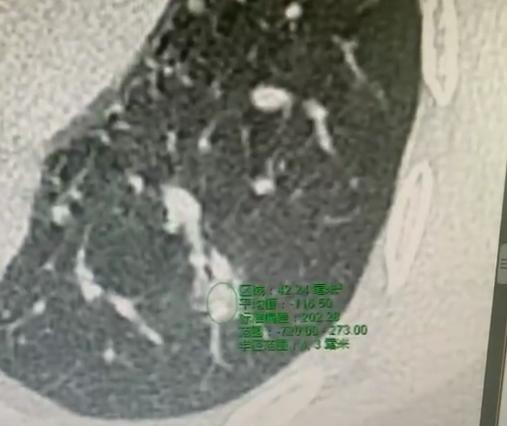

门诊碰到个有意思又让人心疼的患者,43岁,一进门就风风火火的,嗓门都带着急,上来就跟我说:“大夫,您再给我做一次手术吧!” 我当时还愣了下,再做一次? 细问才知道,她刚做完肺部手术满一个月,手里攥着份病理报告,指节都捏白了,神色慌得很。 我让她先坐下来缓一缓,慢慢说。她这才把报告递过来,指着上面“肺浸润性腺癌”几个字,声音都发颤:“大夫,您看这个,我这一个月天天睁眼到天亮,压根没法睡。” 原来她拿到报告后,就天天在网上翻各种科普,越看越慌,说网上好多人说浸润癌恶性程度高,必须得做肺叶切除才能切干净,稍不注意就会复发转移。 她接着跟我吐槽,自己当初做的是肺段切除,现在越想越觉得没切干净,生怕癌细胞扩散,所以特意跑过来,执意要再开一刀。 我听完算是摸清了症结,全是网上的信息搅得他心神不宁,自己瞎琢磨钻了牛角尖。 我把他的片子、病理报告又仔细过了一遍,跟他慢慢解释。他这个结节还不到2厘米,术前我们已经随访观察了一年多,全程都没变化,之前做的PET-CT也显示结节没有高代谢,还带有磨玻璃成分,这些特征都说明肿瘤恶性程度很低。 我还跟他说,日本之前做过相关研究,把这类结节患者分成两组,一组做肺段切除,一组做肺叶切除,随访后发现两组的生存期没差别,反而肺段切除能保留更多肺功能,术后生活质量更高。 我劝他别瞎想,按时做好复查就行,完全没必要再遭一次手术的罪。一番耐心解释下来,他紧绷的肩膀终于放松了,说心里的石头总算落地了,反复道谢后才安心离开。[玫瑰][作揖]